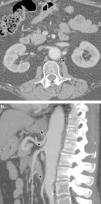

Aortitis is a pathological term designating inflammation of the aortic wall, regardless of its cause. The clinical presentation of aortitis is nonspecific and variable. Symptoms include abdominal pain, fever, and weight loss; acute phase reactants may also be elevated. Aortitis can be caused by a wide spectrum of entities, including from infectious processes to autoimmune diseases (Takayasu arteritis and giant cell arteritis are among the most common of these causing aortitis), and the prognosis and treatment of these entities vary widely. Various imaging techniques can be used to evaluate the lumen and wall of the aorta (such as multidetector computed tomography, magnetic resonance imaging, angiography, or PET-CT). This review focuses on the most common diseases that cause aortitis and on the clinical and radiological findings that are most useful for diagnosing and treating this condition appropriately.